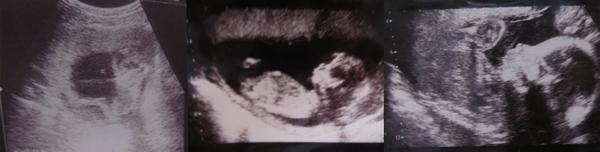

Очень долго сидела на этом сайте , самый лучшей из всех на которых искала нужную инф. по поводу Б.Очень довольна им. Решила наконец тут зарегистрироваться . Нам 29 неделек , будет девочка , имя Катюша

Счастьяяя полнооо))Мы бьемся в полных ход ..здоровенькие , ростем на радость маме )

Ой..и мы когда то были такими крохами )!!Я Вас поздровляю , ростите здоровенькими !!